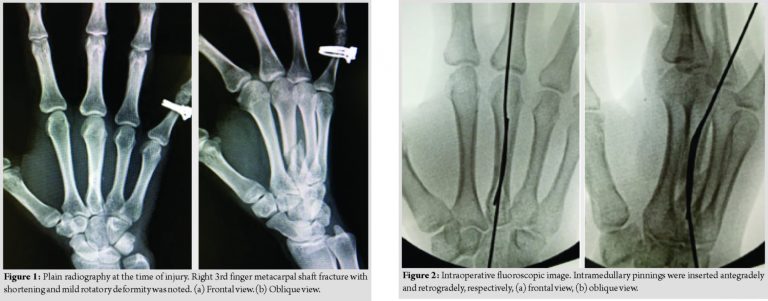

The patient was a 27-year-old female with the right 3rd metacarpal shaft fracture caused by falling down while riding a bicycle. On plain radiography, oblique fracture of the metacarpal shaft with shortening and mild rotatory deformity was noted (Fig. 1a and b). The patient was a professional ballet dancer and requested treatment enabling an early return to exercise and non-noticeable wound.

Surgery was performed under brachial plexus block 6 days after injury. A 1.2-mm mini fixator pin was percutaneously inserted antegradely from the base of the metacarpal bone as an intramedullary pinning and another 1.2-mm mini fixator pin was retrogradely inserted from a site proximal to the Metacarpophalangeal (MP) joint capsule of the metacarpal bone neck as intramedullary pinning (Fig. 2a and b). These pins were inserted through bone holes of cortex made of the same size pins. In addition, the inserted two mini fixator pins were connected using “JuNction” while retaining the manually reduced position to externally reduce and fix the fracture region (Fig. 3a and b). In this technique, the skin incision was not necessary because the pins were inserted percutaneously. The selection of wire diameter was dependent on the diameter of the medullary cavity of the metacarpal bone since two pins should be placed intramedullary. The c-arm is essential because intramedullary pinning was done by fluoroscopy. The operation time in this case was 30 min.